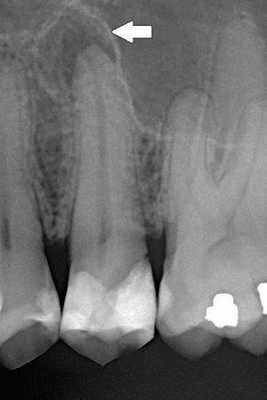

Диагностика периодонтита проводится на основании жалоб пациента, анамнеза заболевания, оценки общесоматического статуса, осмотра головы и шеи, полости рта, зуба, его перкуссии, зондирования и термопробы, электроодонтодиагностики (ЭОМ) и рентгенологического исследования. [10]

ЭОМ — это метод стоматологического исследования, основанный на определении порогового возбуждения болевых и тактильных рецепторов пульпы зуба при прохождении через неё электрического тока.

Чаще всего клиническая картина соответствует острому периодонтиту, за исключением того, что всегда рентгенологически выявляются изменения в тканях периодонта, характерные для той или иной формы периодонтита. [12]